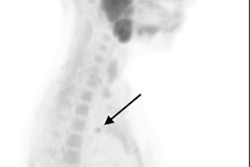

(A) FCH-PET maximum-intensity projection; (B) FCH-PET/CT fusion transverse slice; and (C) low-dose CT transverse slice, showing high FCH uptake in an 11-mm left inferior parathyroid adenoma (arrowheads). The patient underwent minimally invasive parathyroidectomy, leading to normocalcemia during follow-up. No complications occurred.Image courtesy of JAMA Otolaryngology-Head & Neck Surgery